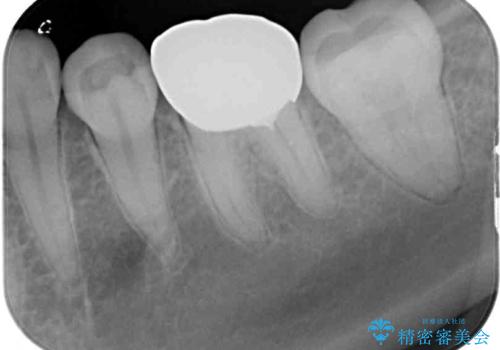

後日状態を確認したところ、残された神経に異常がなかったため、フルジルコニアクラウンにて補綴治療を行いました。